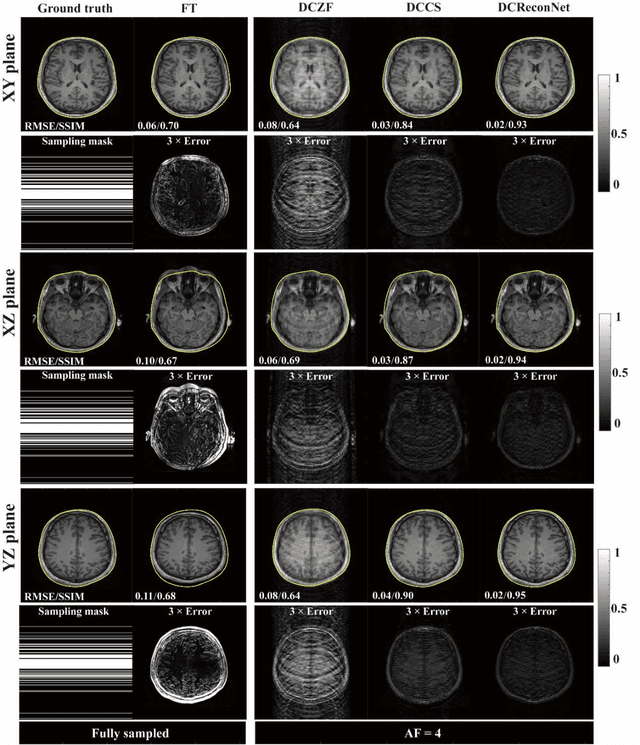

Abstract:Magnetic resonance imaging (MRI) is increasingly utilized for image-guided radiotherapy due to its outstanding soft-tissue contrast and lack of ionizing radiation. However, geometric distortions caused by gradient nonlinearity (GNL) limit anatomical accuracy, potentially compromising the quality of tumour treatments. In addition, slow MR acquisition and reconstruction limit the potential for real-time image guidance. Here, we demonstrate a deep learning-based method that rapidly reconstructs distortion-corrected images from raw k-space data for real-time MR-guided radiotherapy applications. We leverage recent advances in interpretable unrolling networks to develop a Distortion-Corrected Reconstruction Network (DCReconNet) that applies convolutional neural networks (CNNs) to learn effective regularizations and nonuniform fast Fourier transforms for GNL-encoding. DCReconNet was trained on a public MR brain dataset from eleven healthy volunteers for fully sampled and accelerated techniques including parallel imaging (PI) and compressed sensing (CS). The performance of DCReconNet was tested on phantom and volunteer brain data acquired on a 1.0T MRI-Linac. The DCReconNet, CS- and PI-based reconstructed image quality was measured by structural similarity (SSIM) and root-mean-squared error (RMSE) for numerical comparisons. The computation time for each method was also reported. Phantom and volunteer results demonstrated that DCReconNet better preserves image structure when compared to CS- and PI-based reconstruction methods. DCReconNet resulted in highest SSIM (0.95 median value) and lowest RMSE (<0.04) on simulated brain images with four times acceleration. DCReconNet is over 100-times faster than iterative, regularized reconstruction methods. DCReconNet provides fast and geometrically accurate image reconstruction and has potential for real-time MRI-guided radiotherapy applications.